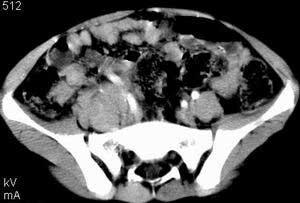

| 患者,男,9岁,因右下腹包块入院,血象不高,不规则发热,常超40度。 平扫: ![]() ![]() ![]() ![]() ![]() ![]() ![]() ![]() ![]() ![]() ![]() ![]() ![]() ![]() ![]() ![]() ![]() ![]() 增强: ![]() ![]() ![]() ![]() ![]() ![]() ![]() ![]() ![]() ![]() ![]() ![]() ![]() ![]() jiajie发言:骶椎右前区不规则软组织肿块,边缘光整,密度均匀,增强后均匀强化,右腹股沟区可见肿大淋巴结,临床有时发热,考虑淋巴瘤,儿童盆腔肿瘤应与神经母细胞瘤和横纹肌肉瘤鉴别。 longzhanghui发言:印象:盆腔右后壁不规则软组织肿块,并向前延伸.似为多个肿块融合,呈中等强化.初步考虑淋巴瘤. 听蝉观竹发言:右侧髂内、外组淋巴结肿大,从其形态和融合的情况看,同意大家意见-----考虑恶性病变,但是9岁男孩还要注意检查睾丸情况,有无隐睾? 常常类似情况是隐睾发生精原细胞瘤淋巴结转移,这个病例也要注意这一点!!! 广东凌发言:大家好,在这里我想说一下个人观点,我建议上传图片的同志能否辛苦一点就是把病史和图片都上传完整一点,比如这个病人的腹膜窗,并且这个病人的肠道的准备也是不怎么好,就从现有的质料看:病灶属于淋巴结肿大当无大的争议,有融合趋势,其内无坏死,边缘强化为主,故考虑:淋巴瘤!建议用腹膜窗看一下和肠道的关系! 阿圣发言:病灶属于淋巴结肿大当无大的争议,有融合趋势,其内无坏死,边缘强化为主,故考虑:淋巴瘤 结果是:淋巴瘤 病例来源:ct762。由宁静致远发布: http://www.radinet.com.cn/forum_view.asp?forum_id=4&view_id=2182 |